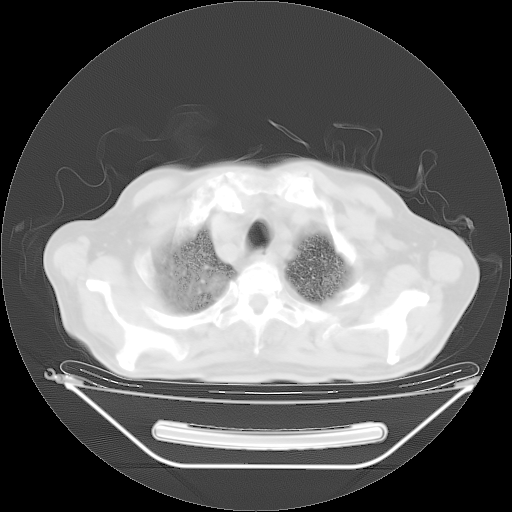

今天复查肺部CT,发现双肺广泛磨玻璃样改变。所以我把3月19日和5月9日相隔50天的肺部CT上传。请大家会诊。

2009年3月19日肺部CT片。

2009年3月19日肺部CT